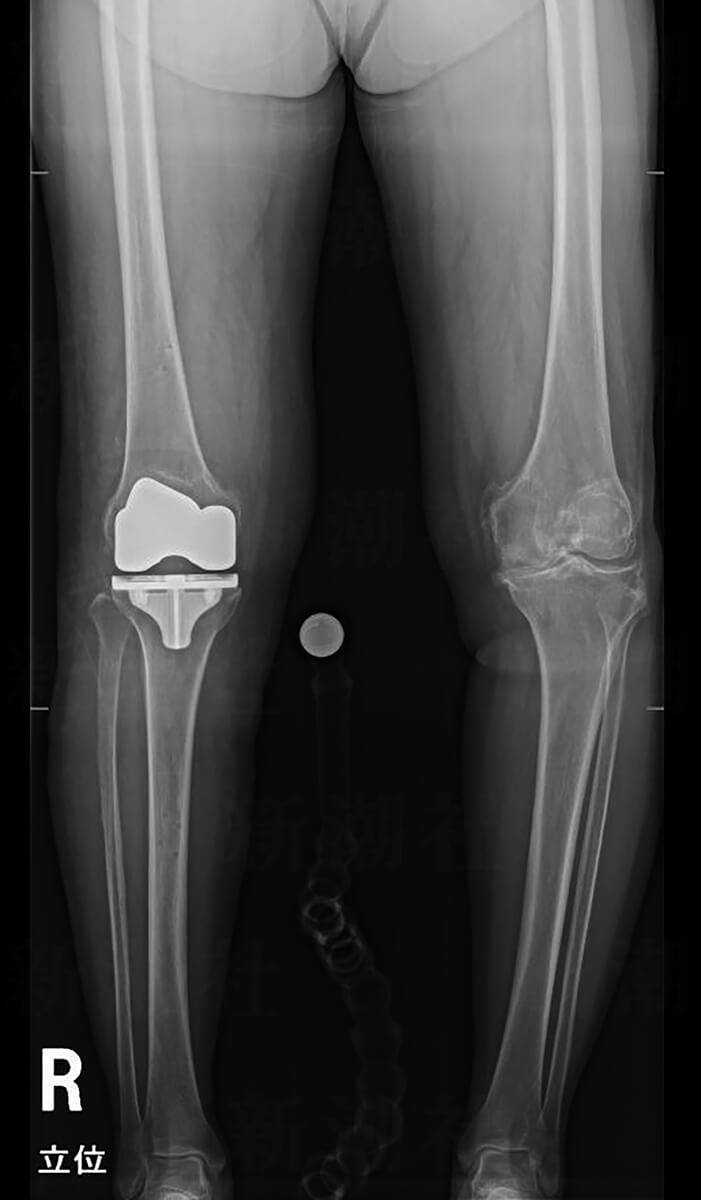

2枚目/5枚中

ライフ週刊新潮 2021年11月18日号掲載

進化する人工関節置換術